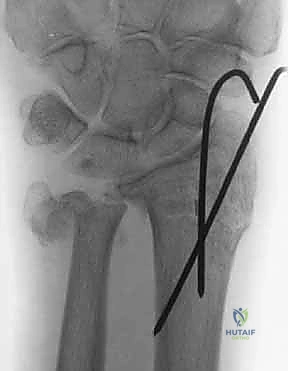

استخدام الأشعة السينية في التشخيص

بروتوكول التصوير الطبي المتقدم

لا يكتفي الدكتور هطيف بالفحص السريري، بل يعتمد على أحدث تقنيات التصوير لضمان "الأمانة الطبية" في التشخيص:

1. الأشعة السينية (X-rays): بوضعيات متعددة (أمامية خلفية، وجانبية دقيقة). الوضعية الجانبية الحقيقية (True Lateral) حاسمة لاكتشاف أي خلع جزئي في المفصل (DRUJ).

2. الأشعة المقطعية ثلاثية الأبعاد (3D CT Scan): تُستخدم في الكسور المفتتة أو كسور رأس الزند المفصلية المعقدة، حيث تعطي خريطة دقيقة للجراح قبل الدخول لغرفة العمليات.

3. الرنين المغناطيسي (MRI): يُطلب عند الاشتباه القوي بوجود تمزقات في الأربطة والمركب الغضروفي (TFCC) التي لا تظهر في الأشعة السينية.